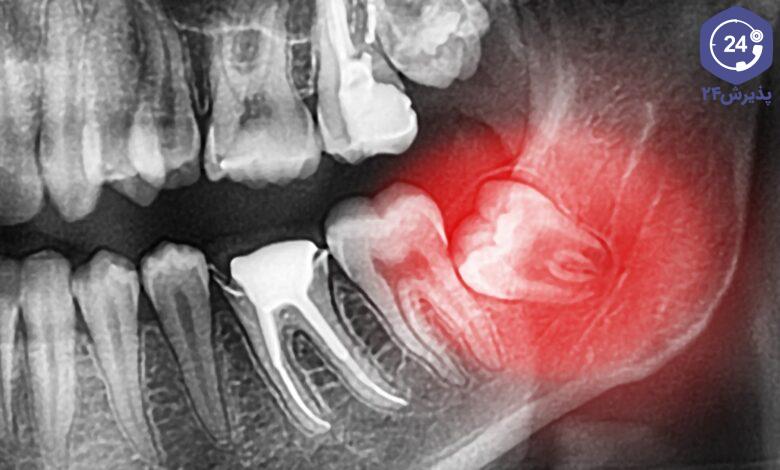

بیشتر بخوانید »دندانهای عقل که به آنها دندان آسیاب سوم نیز میگویند، پشت لثهها قرار دارند و معمولا آخرین دندانهایی هستند که…

بیشتر بخوانید »پوسیدگی دندان از رایجترین مشکلات دهان و دندان است که میتواند علاوهبر درد و سختی، زمینهساز دیگر بیماریهای عفونی مربوط…